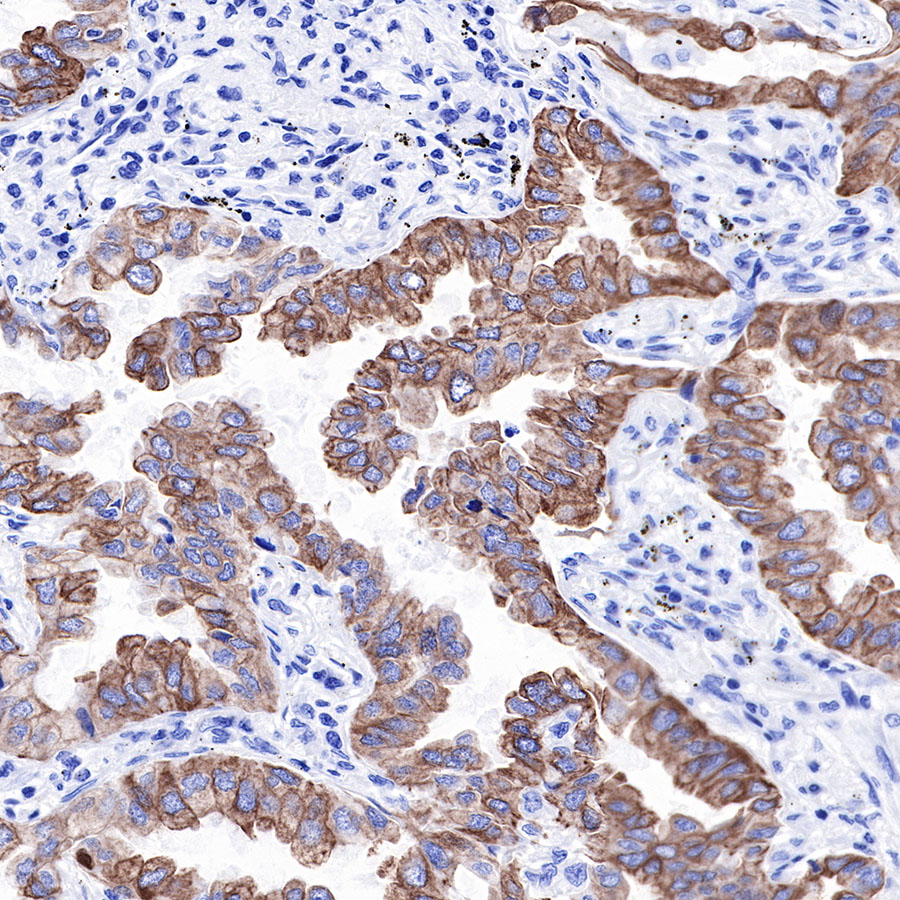

| IHC-P |

1:2000 |

Background

Cytokeratins are proteins of cytoskeletal intermediate filaments, and their main function is to enable cells to withstand mechanical stress. In humans, 20 different cytokeratin isotypes have been identified. Cytokeratins 8, 18, 19, and 20 have been associated with bladder. Cytokeratin 18 (KRT18, also called K18), found in epithelial cells, is released from hepatocytes upon death.